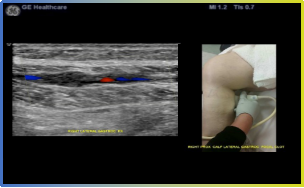

· B-Flow™ 类造影血流 GE专利经典血流技术,基于cSound+™全”芯”平台,对于血流显示能力大幅提升。

· MVI 超微细血流成像 GE专有编码激励技术,混合脉冲连续发射,捕捉组织及病灶的细微低速血流,兼顾穿透力与分辨力。

4、声影同屏 LOGIQ™E11先进的平台算法及数据管理系统,可以将现实中的影像学信息与超声声学信息同时显示在显示屏上,实现智能影像数据管理。丰富临床病案信息,便于远程会诊及跨学科交流。